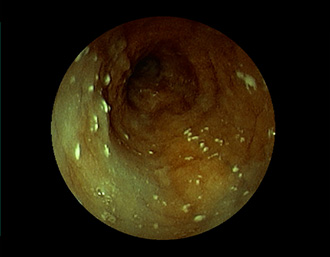

症例1:胃潰瘍(37才、男性)

①胃潰瘍(Stage A1)

健診:胃レントゲン検査で、胃角部ニッシェを指摘され当院受診。

胃角部小弯に、深くて大きな、大きさ約10mmの胃潰瘍(stage 1)

があり、潰瘍底は一部白苔はみ出しを認める。エソメプラゾールマグネシウム水和物投薬で治療開始しました。

(FICE画像)